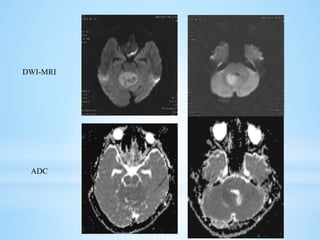

 MRI: There is a high degree of variability of MR appearances of medulloblastoma.

 T1 sequences are usually iso-hypointense to white matter and hyperintense on T2

sequences.

DWI-MRI

ADC